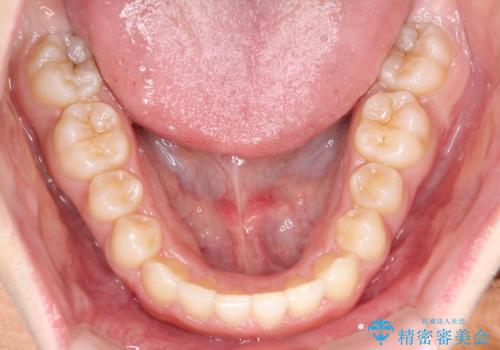

初診時の歯並びの状態としては、上下ともに全体に及ぶの中等度以上のがたつき(叢生)があり、全額的に歯列のアーチが内側に押しつぶされた状態でした。

強い叢生がありましたが、抜歯は行わず上下顎ともに、主に歯列弓の拡大を行い叢生を改善しました。

見た目、嚙み合わせ及び、治療期間や施術内容に大変ご満足いただきました。